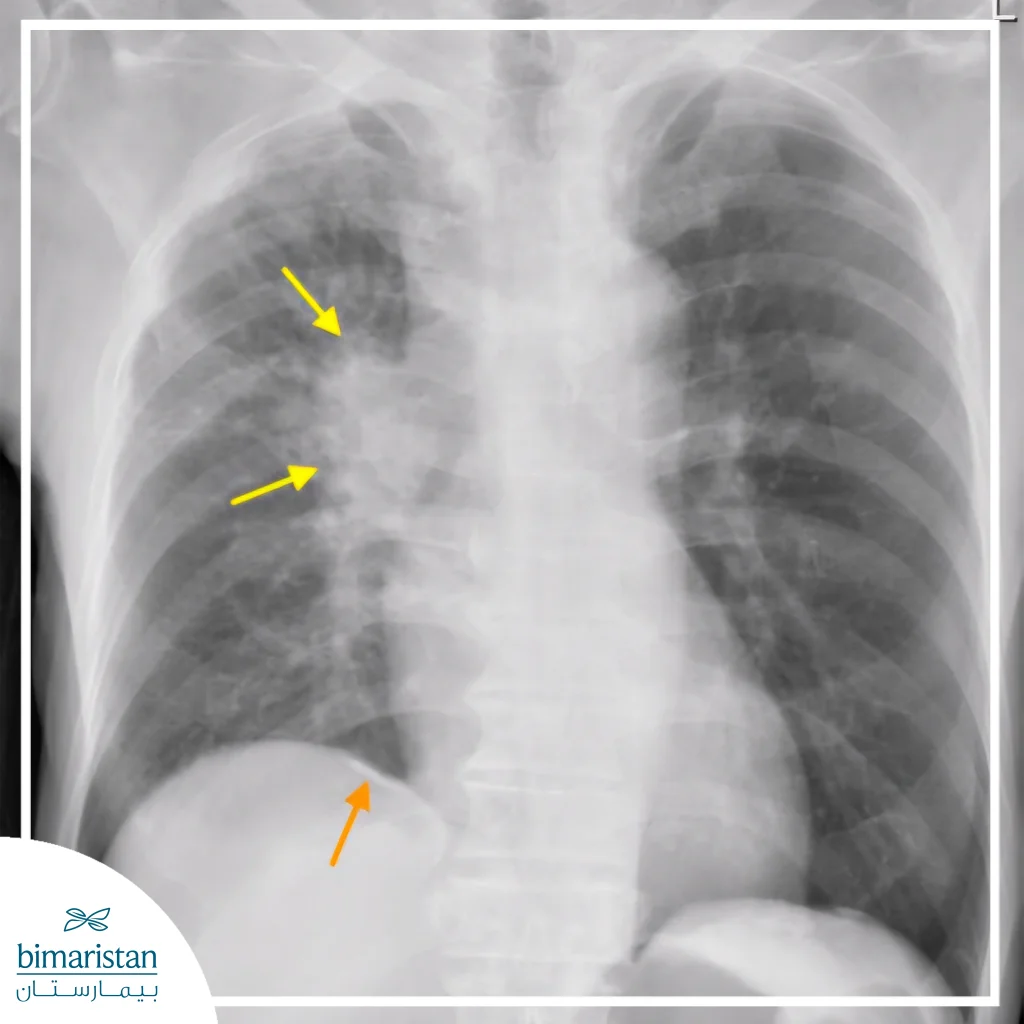

- الفحوص التصويرية: مثل صورة الصدر بالأشعة السينية، والتصوير المقطعي المحوسب، أو التصوير المقطعي بالإصدار البوزيتروني لتحديد أي تغيرات في نسيج الرئة.